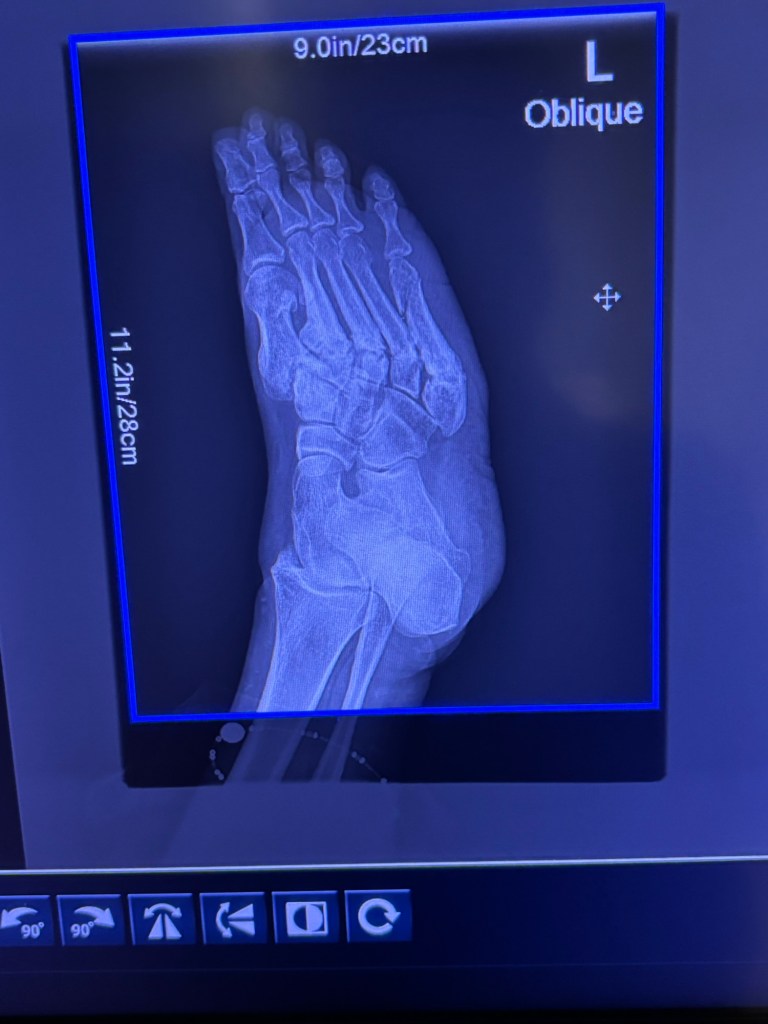

When I did get my X-rays, of course there is my perma-line of micro fractures across the top of my foot – *and* some apparent new ones. 🤦🏻♀️

(Also, the other views suggested some involvement with my ankle so ortho will need to take a look at that. 🤦🏻♀️)